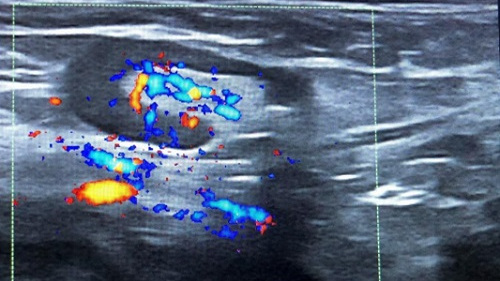

Niño de 7 años que tras vacunación de SARS-CoV-2 presenta bultoma axilar derecho generando asimetría a nivel pectoral. Asintomático. En la exploración física: adenopatía de consistencia elástica, móvil y dolorosa a la palpación. Se realiza ecografía objetivando una adenopatía hipoecoica, ovalada de 15 mm de diámetro anteroposterior, bordes hiperecogénicos bien delimitados e hilio llamativamente grande (Fig. 1) con vascularización central (Fig. 2). Diagnóstico de adenopatía reactiva, con seguimiento ecográfico al mes (Fig. 3) y disminución del tamaño.

Figura 2. Adenopatía hipoecoica con vascularización central